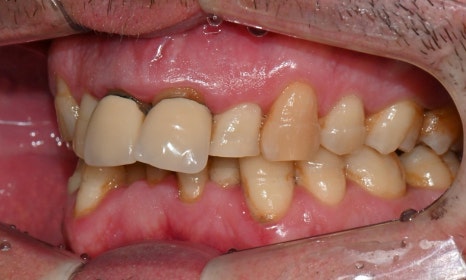

이 환자분은 영국에서 오신 40대 초반 남성분으로, 선천적으로 턱이 작아 어린 시절 턱을 앞으로 이동시키는 악교정 수술과 함께 약 6년 간 치아 교정을 받으셨다고 하셨습니다. 그러나 교정 치료가 충분히 만족스럽게 이루어지지 않았고, 이후 사고로 앞니를 다쳐 보철 치료를 받게 되었습니다. 시간이 지나면서 잇몸이 퇴축되어 앞니 보철물의 금속 부분이 노출되었으며, 제 2급 부정교합 및 불규칙한 치아 배열로 인해 심미적으로 정돈되지 못한 상태로 오랜 기간 지내오셨습니다. 이제는 앞니를 보다 아름답게 개선하고 싶다는 바람으로, 멀리 영국에서 한국까지 내원해 주셨습니다.

진단 결과, 교합시 하악 전치가 거의 보이지 않을 정도로 깊은 교합을 보이고 있었으며, 어린 시절 외상을 입었던 앞니는 치아 뿌리 부근에 광범위한 염증이 관찰되어 장기적인 유지가 어려운 상태였습니다. 이에 앞니 두 개는 발치를 결정하였고, 환자의 비교적 젊은 나이를 고려하여 가능한 한 최대한 치아를 보존하기 위해 앞니 부위 임플란트를 고려했습니다. 그러나 해당 부위 골 손실이 매우 심했고, 외국인 환자로 장기간 내원이 어려운 상황이었기 때문에, 광범위한 골이식을 동반한 임플란트 치료 보다는 비교적 짧은 기간 내에 기능과 심미를 회복할 수 있는 브릿지 보철 치료를 계획하였습니다.

치료가 모두 마무리된 후, 환자분의 미소는 이전과 비교해 전반적으로 한층 더 안정적이고 조화로운 인상으로 개선되었습니다. 앞니의 길이, 형태, 배열이 아랫입술 곡선을 따라 형성되는 smile arc와 자연스럽게 조화를 이루면서, 웃을 때 과도한 긴장감 없이 부드러운 심미적 균형을 회복할 수 있었습니다. 기능적인 교합 안정성과 함께 심미적인 만족도 역시 높게 나타났으며, 환자분도 결과에 대해 매우 만족해하셨습니다.